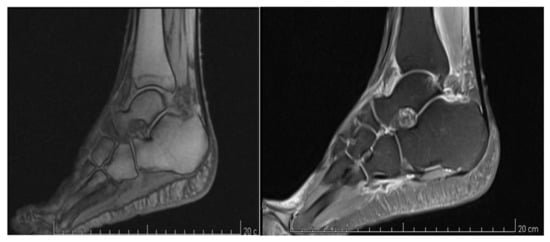

2. Case Presentation